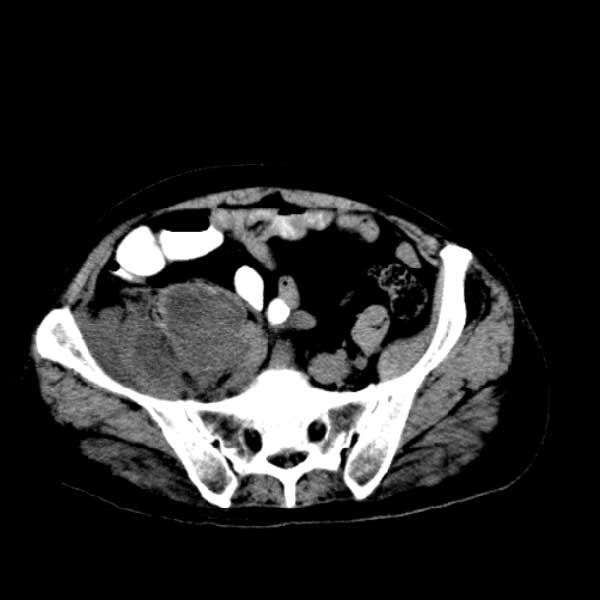

标题: CT13513:男 71 腹部疼痛20余天,近几天高热就诊,骨窗未见异 [打印本页]

标题: CT13513:男 71 腹部疼痛20余天,近几天高热就诊,骨窗未见异

考虑感染性病变可能性大,起源于阑尾?

感染,脓肿形成

考虑为化脓性阑尾炎.脓肿形成.及多肌肉累及.

考虑右侧腰大肌脓肿,向右髂窝、右腹股沟流注。

支持化脓性阑尾炎伴右髂窝脓肿、腰大肌腰方肌脓肿形成。

考虑腹腔及盆腔化脓性炎症,累及右侧髋关节及腹股沟区.

首先考虑化脓性阑尾炎伴腰大肌、腰方肌脓肿,不除外回盲部结核。

回盲部癌待排除。

患者肠镜检查考虑结肠癌,病理证实

患者肠镜检查考虑结肠癌,病理证实。肺部ct可见多发结节,考虑转移